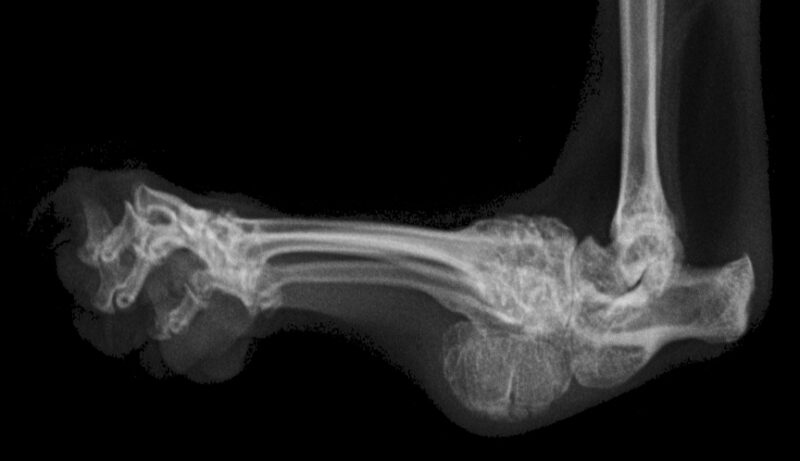

Exemplarisch wird der Fall einer Katze geschildert, die mit 24 Monaten zur Strahlentherapie vorgestellt wurde. Die Patientin sei schon immer schlecht gelaufen, mit Meloxicam als Bedarfsmedikation im Haus allerdings gut zurechtgekommen und habe den Wohnraum auf mehreren Ebenen genutzt. Das Springen auf Kratzbaum und Regale sei regelmäßig üblich gewesen. Innerhalb der vier Monate vor Erstvorstellung sei allerdings eine zunehmende Verschlechterung festzustellen, die trotz einer Erhöhung der Schmerzmedikation deutliche Auswirkungen hatte. Die Besitzer berichten eine deutlich reduzierte Bewegungsfreude, Sprünge über mehr als 50 cm Höhe seien die Ausnahme. Bei der allgemeinen Untersuchung zeigte sich die Katze ängstlich aber aufmerksam und auch bei der Palpation der Gelenke nicht aggressiv. Die Tarsalgelenke stellten sich klinisch deutlich verdickt dar, subjektiv schienen sie etwas verkürzt und geringgradig rotiert.